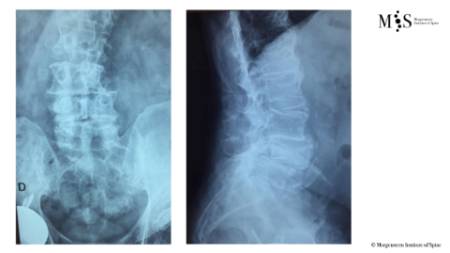

Clinical case example of a lumbar vertebral body resection (corpectomy) and reconstruction of a burst fracture at level L4.

Vertebral body resection (corpectomy) and reconstruction of complex vertebral and burst fractures

Severe vertebral body fractures, i.e. conminute and burst fractures, may require a partial vertebral body resection (corpectomy) and reconstruction with an expandable vertebral body cage. Especially severe fracture cases are also those with a bone fragment moving into the spinal canal that compresses on neural structures, such as the spinal cord and causes spinal canal stenosis. Corpectomy allows to resect most of the fractured body, including the bone fragments pushing on the nerves and intruding into the spinal canal. The vertebral body reconstruction is usually rounded up with a posterior augmented instrumented fusion of the adjacent levels to the fracture. All of this allows a proper healing of the fracture and the patient to recover without pain.